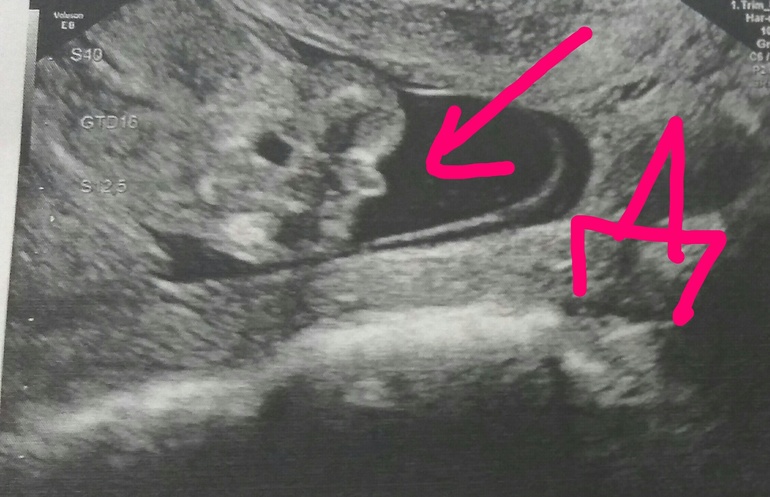

Особенности УЗИ при определении пола ребенка

Раздел: Идеи и советы